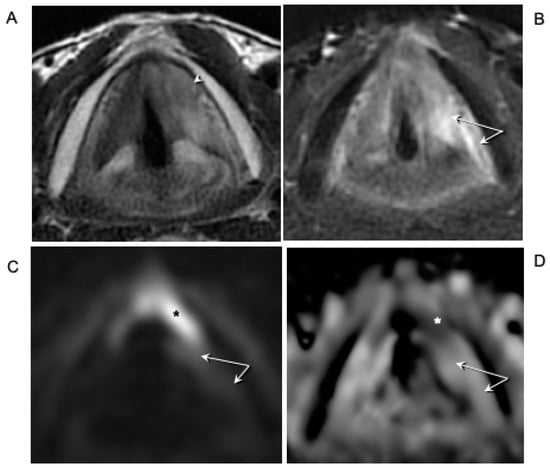

- Glottic carcinoma involving the IPGS and extending toward the CAU, medially contained by the conus elasticus and laterally by the thyroid wing (Figure 3):

- The tumor extends in part to the SPGS becoming transglottic.

- It involves TAM, IPGS, thyro-arytenoid space and/or posterior crico-thyroid space and blocks the arytenoid laterally corresponding to the lateral crico-arytenoid muscle; the tumor involves or invades the arytenoid but not the cricoid (that can present signs of sclerosis anyway), and there is the strong doubt about CAJ involvement, even if in part.

- The eventual infraglottic extension, evaluated exactly at the free edge of the TVC midline, is ≤10 mm.